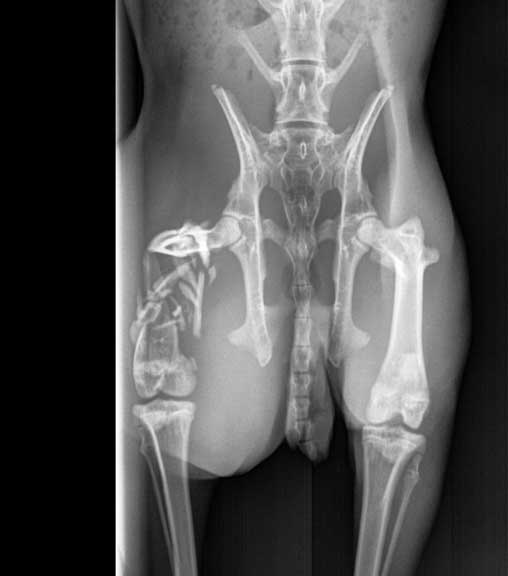

- Comminuted fracture means the bone is in pieces. The femur in the radiograph below is an example.

This femur is in 10 pieces

After a thorough physical exam and stabilization, radiographs were obtained. Sometimes surgery is needed, as in this case of a rabbit with a distal transverse fracture of the femur (thigh bone). In this page you will see a femur fracture surgery.

The arrow points to the fracture on this lateral view

The fracture from a different view showing its severity